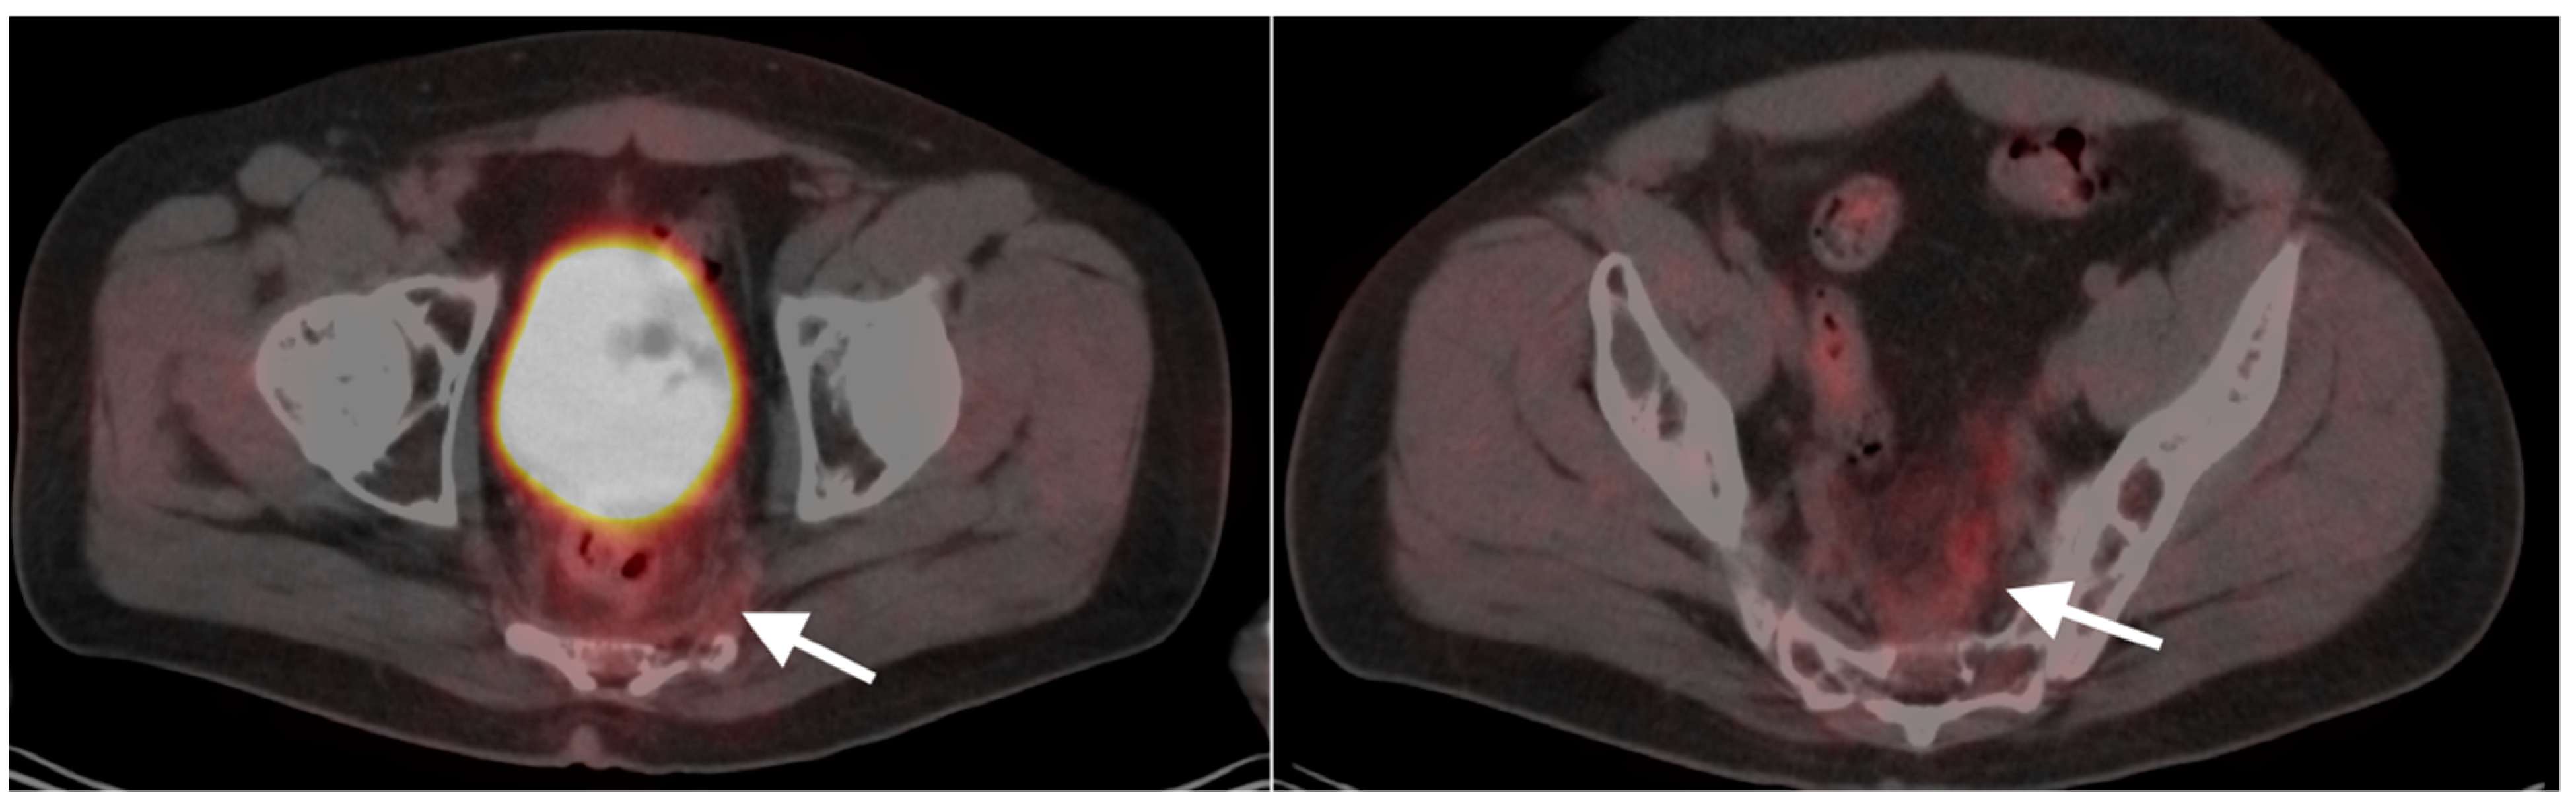

9. Bowel Adenocarcinoma: Colon, Rectum, Small Bowel